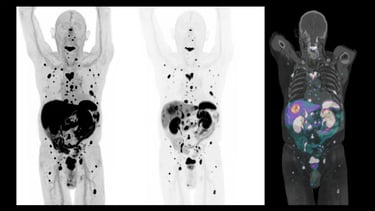

Uma dúvida comum entre os pacientes é sobre quais exames são necessários para avaliar a extensão da doença. Muitas pessoas acreditam que exames mais modernos, como o PET-CT, são sempre a melhor escolha, mas isso não é uma regra. Cada exame tem indicações específicas e deve ser escolhido com base no tipo de câncer e nos objetivos da investigação.

Ilustração: Imagem de PET-CT (PET SCAN), mostrando metástases.